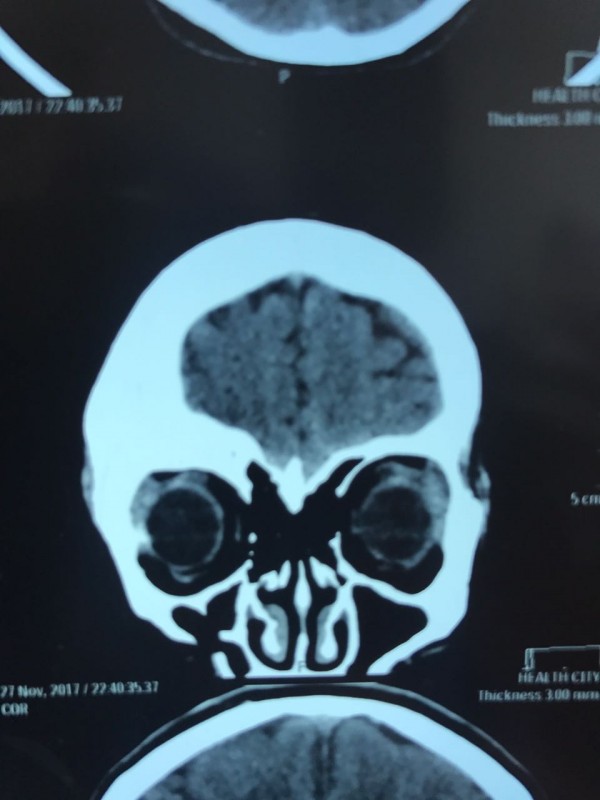

"Компьютерная томография показала, что костная опухоль поражала лобную кость и "крышу" орбиты глаза, которая, в свою очередь, сдавливала глазное яблоко. Чтобы убрать опухоль, потребовалось немало времени. Наша задача была сохранить глазное яблоко, зрительный нерв и сосуды. Если неправильно провести операцию и неправильно закрыть дефект, то в последующем это может привести к эстетической неполноте и асимметрии лица. Уникальность еще и в том, что в операции применялась 3D-стереолитография, которая делается только в Алматы", - рассказал он.

Снимок сделан после операции. Фото предоставлено Константином Ли